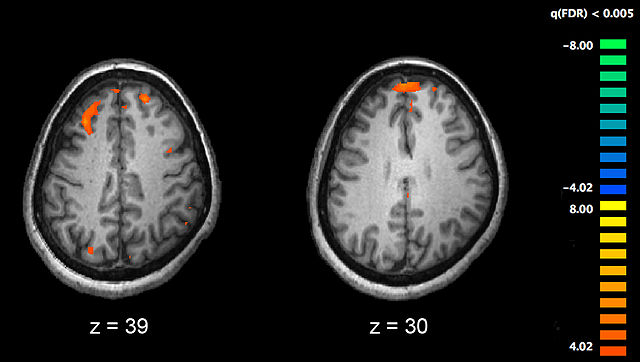

English: Image showing brain areas more active in controls than in schizophrenia patients during a working memory task during a fMRI study. Two brain slices are shown.

Source PLoS One. 2010 Aug 11;5(8):e12068. An event-related FMRI study of phonological verbal working memory in schizophrenia.doi:10.1371/journal.pone.0012068.g002. PMID 20725639

Cropped from the full original image, leaving only the substraction between patients and controls. All p-values are corrected with false discovery rate of q<0.005.